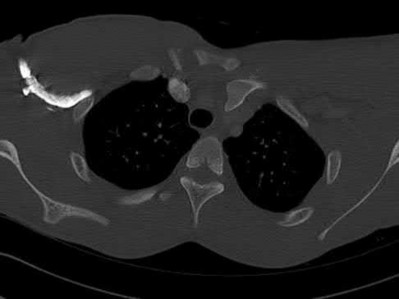

2. # A 35-year-old woman is involved in a head-on collision while driving. Initial radiographs are shown in Figures 8a and 8b. Injury to what vessel increases the risk for osteonecrosis of the injured bone?

5. Artery of the tarsal sinus Corrent answer: 4

The patient has a Hawkins type III talar neck fracture-dislocation with a risk of osteonecrosis ranging from 69% to 100%. Anatomic studies have shown that the artery of the tarsal canal supplies the lateral two thirds of the talar body.

The other vessels listed provide no significant contribution to the talus.